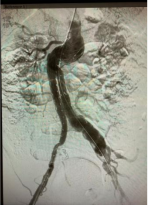

腹主动脉瘤手术方式包括:1、外科开腹人工血管置换手术。开腹手术面对已出现渗漏的腹主动脉瘤治疗有方便止血优势,但手术创伤大,需要输血,病人不易耐受。2、微创介入腔内覆膜支架植入术。腹主动脉覆膜支架腔内隔绝术手术的优点是降低围手术期死亡率,合并多基础病的腹主动脉瘤患者更容易耐受,潜在优点包括降低手术耗时、减轻疼痛和创伤、缩短住院时间和外科监护时间、减少输血。